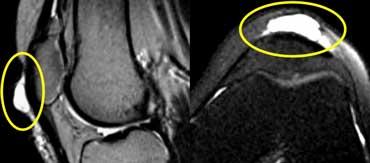

TRÁI: Rách một phần gân cơ tứ đầu đùi. Chỉ có gân cơ thẳng đùi bị rách (mũi tên xanh). PHẢI: Bệnh lý gân có từ trước (vòng tròn vàng) trên ảnh mặt phẳng ngang.

Một ví dụ khác về rách một phần gân cơ tứ đầu đùi.

Rách hoàn toàn gân cơ tứ đầu đùi. Ảnh chuỗi xung T2W mặt phẳng đứng dọc. Mất liên tục hoàn toàn. Khối máu tụ ở giữa.

Khi không còn sự liên tục giữa xương bánh chè và gân cơ tứ đầu đùi, đó là rách hoàn toàn.